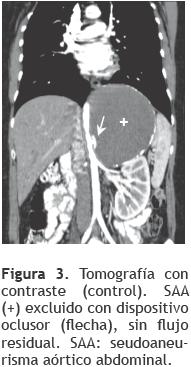

No hubo complicaciones durante el procedimiento. Tiempos de procedimiento y fuoroscopía 100 y 20 minutos, respectivamente. A las 72 horas, se otorgó el alta hospitalaria. Cinco meses después, la paciente permanece asintomática, con el SAA trombosado y sin flujo residual en el control tomográfico (Figura 3) y por Doppler color.

Comunicamos un paciente, a quien 10 años después de una herida abdominal por arma de fuego, se le diagnosticó un SAA de 17 x 13 cm, con cuello corto, originado cercanamente al ostium del tronco celíaco, formando un ángulo agudo con el eje aórtico. Realizamos la exclusión del mismo, con un dispositivo diseñado para el cierre de comunicación interauricular (CIA), utilizando el acceso braquial izquierdo, debido a la angulación del cuello del defecto. No hubo complicaciones, a las 72 horas se otorgó alta hospitalaria. El control tomográfico al mes, mostró el falso aneurisma de igual tamaño y sin flujo residual. A los cinco meses de seguimiento, la paciente permanece asintomática.